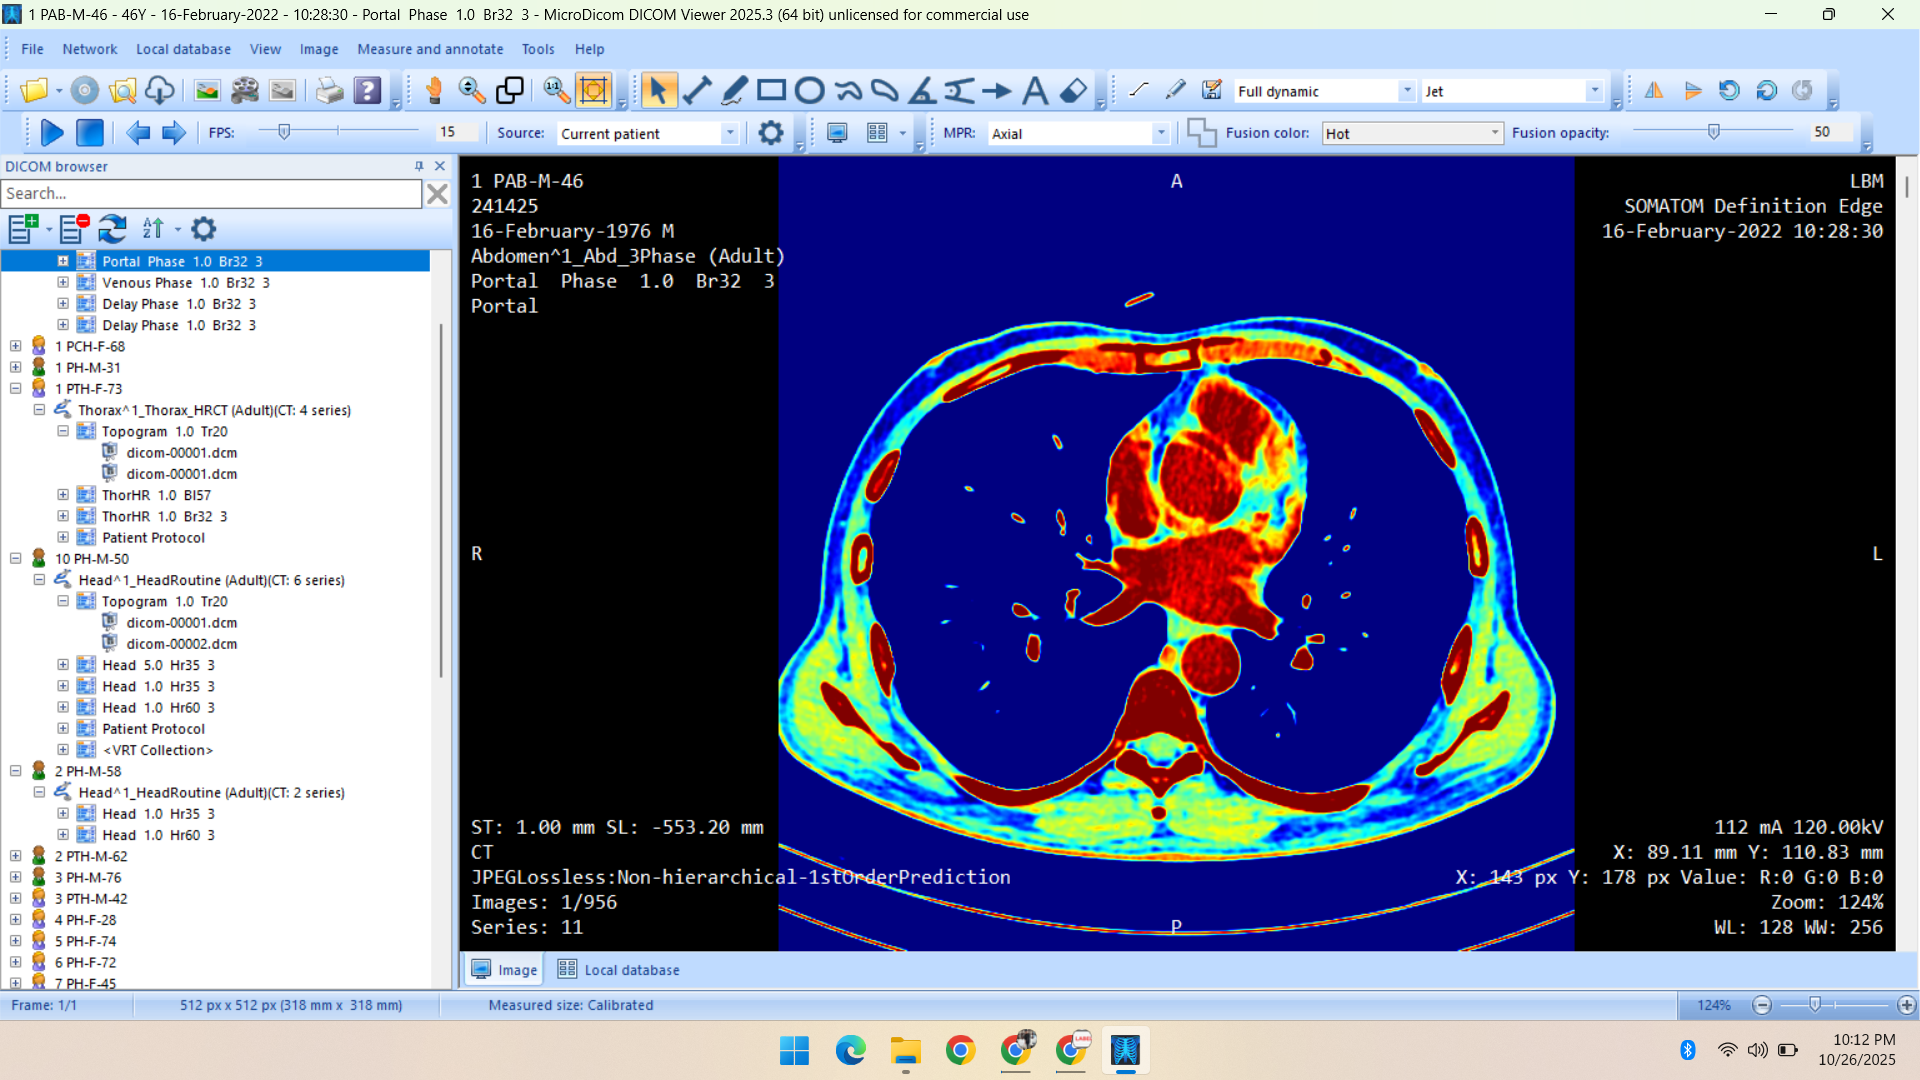

- Radiology Data – CT Scans, X-Rays, MRI, Echocardiography, Ultrasound.

Deep specialization in radiology, pathology, and histopathology datasets, annotated with medical precision.

Healthcare & Medical Data Supply

We specialize in healthcare datasets including radiology (CT, X-ray, MRI, Ultrasound, Echocardiography), pathology microscopy, and histopathology images — all ethically sourced and research-ready.

- CT Scan